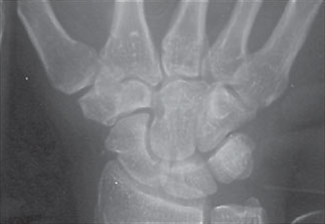

- Positivt fund på røntgen eller MR